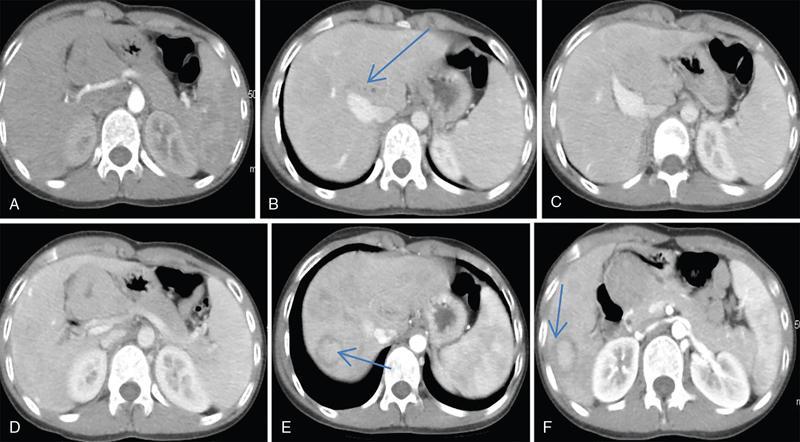

Ritu K. Kashikar, Shrinivas B. Desai, Payal Agrawal A spectrum of vascular variants can involve the liver. Both congenital and acquired anomalies can be seen. The abnormalities can involve the portal venous system, hepatic artery, hepatic veins or maybe the result of shunting between any of these vessels. Though not commonly encountered, familiarity with the pathogenesis and imaging features of these vascular entities can guide appropriate patient management. This chapter aims at classification of vascular pathologies of the liver (Table 9.12.1) with description of important entities. The umbilical vein accounts for approximately 80% of the afferent flow into the liver in utero. The umbilical vein joins the left portal vein, which in turn drains into the ductus venosus and carries blood to the inferior vena cava. The umbilical vein and ductus venosus start involuting at birth and typically close in the first week of life in term neonates (Fig. 9.12.1). Detailed embryology of the portal venous system has been discussed in previous chapters. The portal vein accounts for two-thirds of the hepatic blood supply. The distinctive feature of the portal vein is that it begins and ends in capillaries. The blood from the entire gastrointenstinal tract (except lower rectum), gallbladder, pancreas and spleen is carried via the portal vein to the liver. The hepatic arterial branches divide along the distribution of portal venous radicals and supply oxygenated blood to the sinusoids (Fig. 9.12.2). These include The dorsal and ventral limbs of the vitelline vein form the normal portal vein. Atrophy of the ventral limb occurs during embryogenesis. This maybe an incidental finding, though association with duodenal obstruction is seen in 50% cases. The aetiology of duodenal obstruction is often due to secondary causes such as duodenal stenosis, atresia, Ladd bands due to malrotation or annular pancreas. Associations include heterotaxy (polysplenia) and biliary atresia. Aberrant vessel may give an extrinsic impression on the high second portion of the duodenum on upper GI series. USG may show aberrant vessel in patients being scanned for other anomalies. The aberrant vessel is usually incidentally discovered intraoperatively during surgery for duodenal obstruction or malrotation. Hypoplasia or atresia of the portal vein may involve all or a portion of the portal vein. Atresia of a major branch is associated with absence of the corresponding hepatic lobe. Main portal vein hypoplasia or stenosis results in prehepatic portal hypertension and gastrointestinal hypertension (Flowchart 9.12.1). A portal vein smaller in calibre or as small as the adjacent hepatic artery is termed hypoplastic. The venous diameter in cases of hypoplasia is of 3 mm. Twenty-six per cent cases with biliary atresia have hypoplastic portal vein. TAPVR is a congenital cardiac malformation in which pulmonary veins instead of draining into left atrium during cardiac development, drain into the right atrium via an anomalous vein, resulting in right to left shunts. Types: In type 3 TAPVR an anomalous infradiaphragmatic vertical vein is formed by the confluence of pulmonary veins, typically through the oesophageal hiatus. Venous obstruction at the level of the diaphragm and accounts for the clinical presentation of pulmonary venous congestion and oedema. Early presentation (within 24–36 hours of life) included respiratory distress with cyanosis, tachypnea, and tachycardia. Features on X-ray include normal–sized heart with pulmonary interstitial oedema. One-third of patients have an additional complex cardiac anomaly and heterotaxy with right atrial isomerism. May show abnormal draining vein draining into the IVC or pulmonary vein. CT/MR venography allows accurate depiction of the anomaly. The pulmonary venous confluence drains to systemic veins below the diaphragm. The confluence is usually posterior to the left atrium and vertically oriented. From here, a descending vein passes through the oesophageal hiatus and most frequently drains into the connection in to ductus venosus, hepatic veins or inferior vena cava is not as frequent. Portosystemic shunts are classified into intrahepatic and extrahepatic. In the intrahepatic shunts, the shunt is at the level of PV branches after its division whereas in the extrahepatic shunts the anastomoses are between the tributaries of the portal or mesenteric system or main PV and a systemic vein (Flowchart 9.12.2). Abernethy malformation, also known as congenital extrahepatic portosystemic shunts (CEPS) is a rare clinical entity, in which portal blood is shunted partially or completely into the systemic circulation via an abnormal communication of the portal system with the systemic circulation. It results from persistence of embryonic vessels. The entity was named by John Abernethy in 1793. The embryological development of the portal vein occurs between the 4th and 10th weeks. The umbilical veins of chorionic origin, vitelline veins and the cardinal veins from the body of the embryo are the three paired venous systems seen in the embryo in the 4th week. Communications develop between the vitelline veins at 4 weeks, which anastomose to form a figure-of-eight configuration around the developing duodenum. Selective involution of these veins leads to the final configuration of the portal vein. Because the vena cava also has a complex development and is derived from several venous channels including the sinus venosus and a portion of the anastomosis between the right and left vitelline veins in the cranial part of the liver, it has been suggested that this may be the embryological basis of development of congenital extrahepatic portosystemic shunts. Various systems have been proposed for classification of Abernathy Syndrome: In this classification portal flow is classified as Patients with type A drainage show associated cardiac anomalies, while gastrointestinal bleeding is common in type C. In this system CEPS was classified into three types depending on the degree of severity of intrahepatic portal system hypoplasia in to mild, moderate and severe types. This system has therapeutic implications in providing information regarding acceptance of portal blood flow by the portal vasculature after shunt occlusion. CEPS may be asymptomatic well into adulthood and many authors have reported seeing adult patients presenting for the first time with clinical manifestations. Clinical features of portosystemic shunts may broadly be divided into: These include hepatopulmonary syndrome, metabolic dysfunction and hepatic encephalopathy. Patients with type 1 shunt have a female preponderance and often have concomitant congenital anomalies. These anomalies are less common in patients in type 2 shunts. Other anomalies have also been reported in patients with Abernethy malformation which include chromosomal anomalies such as Downs syndrome and structural anomalies of the heart, gastrointestinal, genitourinary, skeletal and vascular systems. Approximately half the patients of CEPS have nodular lesions of some sort in the liver (Flowchart 9.12.3). Nodular hepatic lesions in patients with congenital portosystemic shunts may be single or multiple. In order to establish a diagnosis of CEPS a communication between the portal and the systemic venous system, either before or after the formation of the PV by union of the SMV and SV has to demonstrated. Secondary causes of nonvisualization of the PV such as portal cavernoma or PV thrombus should be excluded. Patients with congenital portosystemic shunts do not have features of portal hypertension, such as splenomegaly, varices and collaterals. USG may demonstrate the shunt and show haemodynamics involved such as the magnitude and direction of flow. It may pick up congenital shunts preoperatively; however, it may not detect associated anomalies particularly of lung and heart. Smaller shunts, particularly type 1a may not be well picked up. Ultrasound may not fully characterize liver lesions seen in these patients. It is the modality of choice and can accurately diagnose the shunt and type and aids in management. Shunt is visualized as an abnormal communication between the portal venous and systemic circulation and is best depicted in the portal venous phase. CT also shows presence/absence of intrahepatic branches of portal vein. Evaluation of associated anomalies particularly in patients with congenital heart disease who require evaluation of pulmonary vasculature, or patients with suspected hepatopulmonary syndrome who require evaluation of the lungs can also be done with CT (Fig. 9.12.4 and Table 9.12.3). Another major advantage of CT is that it helps to detect and characterize hepatic lesions in these patients. It displays the arterial and venous anatomy, and provides an angiographic road map for surgical resection. Regenerative nodules are usually homogeneous with enhancement during arterial phase, on both CT, however without washout (Fig. 9.12.5). Rest of lesions show classic enhancement pattern as described in previous chapters. The imaging findings in patients with Abernethy malformation with hepatocellular carcinoma do not appear to be typical, that is hypervascularity on the arterial phase images with washout on delayed phase. Thus, patients who do not have typical findings of a benign lesion, that is lack of arterial enhancement, should be closely followed up or biopsied. Disadvantages of an MRI include longer periods of sedation which is a disadvantage in patients with CEPS who may be very young, very hypoxemic or encephalopathic. MRI also has lower spatial resolution than CT and may not show small intrahepatic portal venous radicles in type 2 patients. MRI can otherwise show all abnormalities seen on CT. Advantages of MRI using hepatobiliary contrast agents are in the characterization of hepatic nodules and for follow-up. MRI does not expose the patients to ionizing radiation. Patients with no symptoms, those with mild metabolic abnormalities and with liver nodules should be followed up with ultrasound and biochemistry. Patients with portosystemic encephalopathy, liver dysfunction or those with shunt ratio >60% should be treated according to type of shunt. Patients with type 1 shunts should be transplanted. Patients with type 2 shunts should be treated with shunt closure – either via embolization or surgical. Liver transplantation is considered when medical and surgical methods fail especially in patients with complications. Intrahepatic portosystemic shunts are rare. They may be congenital or result from trauma or portal hypertension. They develop due to persistent communications between vitelline and umbilical systems. These are communications between the branches of the PV and inferior vena cava (IVC). Park et al. classified these 1990 in four types. Type 5 was added later, these are classified in Table 9.12.4. Type 2 shunt with or without a focal varix is the most common type reported. Another classification system is proposed by Kanasawa et al. based on correlation with severity of portal hypoplasia (mild, moderate and severe) with portal venous pressure, histopathological findings, postoperative portal venous flow and hepatic regeneration. Associated anomalies such as cardiovascular, hepatobiliary, urogenital and gastrointenstinal can be seen. Complications such as portopulmonary hypertension are seen in 13%–66% children. As a consequence of long-term shunting, hepatic encephalopathy, and hepatopulmonary syndrome are the most common symptoms. Tumours such as FNH and regenerating nodular hyperplasia can be seen. These shunts may close spontaneously within the first 2 years of life or may remain asymptomatic and undetected for several years. When chronic shunting persists into adulthood, patients most often present with encephalopathy. The feeding (afferent) and draining (efferent) vessels of the shunt appear as enlarged, tubular, anechoic structures that are contiguous with the portal and hepatic veins. Antegrade flow is seen on colour Doppler images. Focal varix if present appears as an abnormal, rounded cystic structure with turbulent flow. Doppler study can also calculate the shunt ratio (total blood flow volume in the shunt divided by the blood flow in the portal vein). Shunt ratios greater than 60% should be corrected to prevent complications. Loss of normal undulating waveform of afferent portal vein branch with increased flow velocity and phasic waveforms owing to transmitted cardiac pulsations can be seen. The efferent hepatic vein branch of the shunt can show continuous flow with flattening of the Doppler waveform due to increased portal venous inflow. Communication between intrahepatic portal venous and peripheral hepatic venous radicals can be demonstrated easily on both contrast-enhanced CT and MRI. Similar to extrahepatic shunts CT is preferred over MRI in documentation of shunts. The afferent portal vein branch and the efferent hepatic vein branch are enlarged. Venous varices can be seen. The draining hepatic vein branch opacifies earlier than other hepatic veins (Fig. 9.12.6 and Table 9.12.5). The liver may show fatty degeneration and atrophy, but when the anomaly is corrected, fatty replacement disappears and liver size increases. Conservative medical therapy including restriction of protein and ingestion of lactulose. Symptomatic intrahepatic portosystemic shunts can be managed conservatively or with transcatheter embolization, surgical ligation or partial hepatectomy. The connection between the left umbilical vein and right hepatocardiac vein (future IVC) in the foetal circulation is called ductus venosus. This vessel is responsible for carrying nutrient-rich blood from placenta to the right atrium directly by bypassing the sinusoidal plexus of the liver. The umbilical vein and ductus venosus close at birth and form the ligamentum teres and ligamentum venous, respectively. The time interval following birth for closure of ductus venosus is variable ranging from few minutes after birth to 18 days in term neonates and as late as 37 days in premature infants. Patent ductus venosus is an intrahepatic portocaval shunt causing partial or complete diversion of portal blood to the systemic circulation and may present with hyperammonemia. Patent ductus venosus is seen on Doppler sonography as a vascular tubular structure in the left lobe of the liver, continuing from the umbilical vein and connecting the portal vein to the inferior vena cava. The foetal ductus venosus show waveforms similar to IVC corresponding to the cardiac cycle with a systolic and diastolic component. This diphasic waveform is seen in preterm and term infants and becomes monophasic as ductus closes. CT and MRI also accurately detect the shunt and patency. Associated hepatic lesions seen in patients with portosystemic shunts can be diagnosed and characterized better. Treatment (closure) is recommended in cases with complications or to prevent complications if the shunts persisted beyond 2 years of age. Shunt closure can be performed surgically or endoscopically. The complex nature of the shunt can pose problems during surgical closure. Transvenous and balloon occlusion have been done successfully. Occlusion of portal vein can occur due to a variety of conditions. The aetiologies of portal venous thrombosis in the neonatal age group include umbilical vein catheterization, omphalitis, dehydration or neonatal sepsis. Older children develop occlusion secondary to intraabdominal infections and portal hypertension. Other aetiological factors include prothrombotic states such as hereditary deficiency of protein C or protein S and factor V Leiden deficiency, vascular injury, trauma, stasis and congenital anomalies such as webs. Acute portal vein thrombosis can be asymptomatic, or the patient may present with abdominal pain, ascites or fever. Chronic portal vein thrombosis presents as ascites, encephalopathy, varices and upper gastrointestinal bleeding. Acute thrombus appears hypoechoic filling defect on USG with absent flow on Doppler. There is distension of the thrombosed vein (Fig. 9.12.7). CT and MRI with contrast will detect filling defect in the vein with distension. T2W1 images may show absence of flow void. Acute thrombus may appear hyperintense on T1W1 images. Tumour thrombus reveals signal similar to tumour on all sequences with diffusion restriction (Fig. 9.12.8). Chronic thrombus may present as eccentric filling defect, attenuation of vein or less commonly calcification of vessel wall. Collaterals are often seen in chronic portal vein thrombosis. Treatment usually involves combination of anticoagulation and intervention depending on age of thrombus. An acute portal venous thrombus may undergo partial or complete spontaneous resolution. The commonest cause of paediatric portal hypertension in the developing world is extrahepatic portal vein obstruction (EHPVO). It is also the second most common cause of portal hypertension in the western world. EHPVO is a condition characterized by obstruction of the extrahepatic portal vein (as the name suggests) with or without associated involvement of the intrahepatic branches, splenic vein (SV) or superior mesenteric vein (SMV). The hallmark of this chronic longstanding condition is carvernomatous transformation of the portal vein. Acute and chronic portal vein thromboses occurring in the setting of liver cirrhosis or HCC are not included in this disorder. EHPVO is an important cause of noncirrhotic portal hypertension with preserved liver structure and function till late in course of the disease. Proposed aetiologies include infection or prothrombotic event occurring early in life (in genetically predisposed individuals), leading to portal venous occlusion (Table 9.12.6).